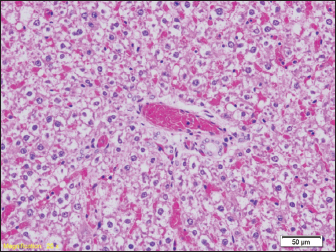

Fig. 8. Signs of hydropic and vacuolar degeneration in epithelial cells of renal tubules (HE, ×200). Brain tissue samples of all groups of rats show a lower or higher degree of edema (Fig. 9).

Signs of hydropic and vacuolar degeneration can be seen in the kidney samples of all groups of rats, and signs of acute tubular necrosis can be seen in one of the samples (group G2) (Figs. 7 and 8).

Signs of hydropic and vacuolar degeneration can be seen in the kidney samples of all groups of rats, and signs of acute tubular necrosis can be seen in one of the samples (group G1).

The pathohistological findings of the kidneys in all examined groups indicate hydropic and vacuolar degeneration of the epithelial cells of the renal tubules, and the pathohistological findings of the brain in all groups show signs of pericellular and perivascular edema. In our study, we did not find diatoms in the kidneys. Previous studies prove that the number of diatoms found may be lower than expected, as in liver samples. Since the middle of the last century, there have been certain disagreements among numerous authors about the reliability of diatom findings in internal organs such as the kidney, liver, or bone marrow. The reason for this is the high rate of occurrence of false positive findings (Timperman, 1969).

The results of the pathohistological examination of the kidneys in our study coincide with those of other authors. In previous studies, after drowning, signs of glomerular enlargement with hypercellular changes were found on the kidneys, signs of degeneration were present in the tubules, such as their uneven expansion and edema of the cells of the tubular walls, and in the interstitium, there were congested capillaries were present (Ibrahim et al., 2022). Seong et al. (2012) also reported signs of acute tubular necrosis after drowning (Seong et al., 2012).